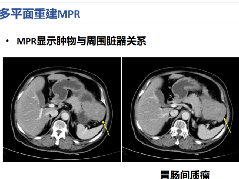

| 类 型 | 影像表现 | 小 结 |

| 布加综合征(图4 和图 5) | 肝脏体积增大,密度弥漫性减低(由肝实质充血造成)。 | 在肝内静脉、肝静脉或下腔静脉肝上段流出道梗阻。少见,与髙凝状态、口服避孕药、怀孕、浸润性肿瘤和先天性瓣膜有关,“翻转”式对比增强(见图5)。 |

图4布加综合征

图5布加综合征